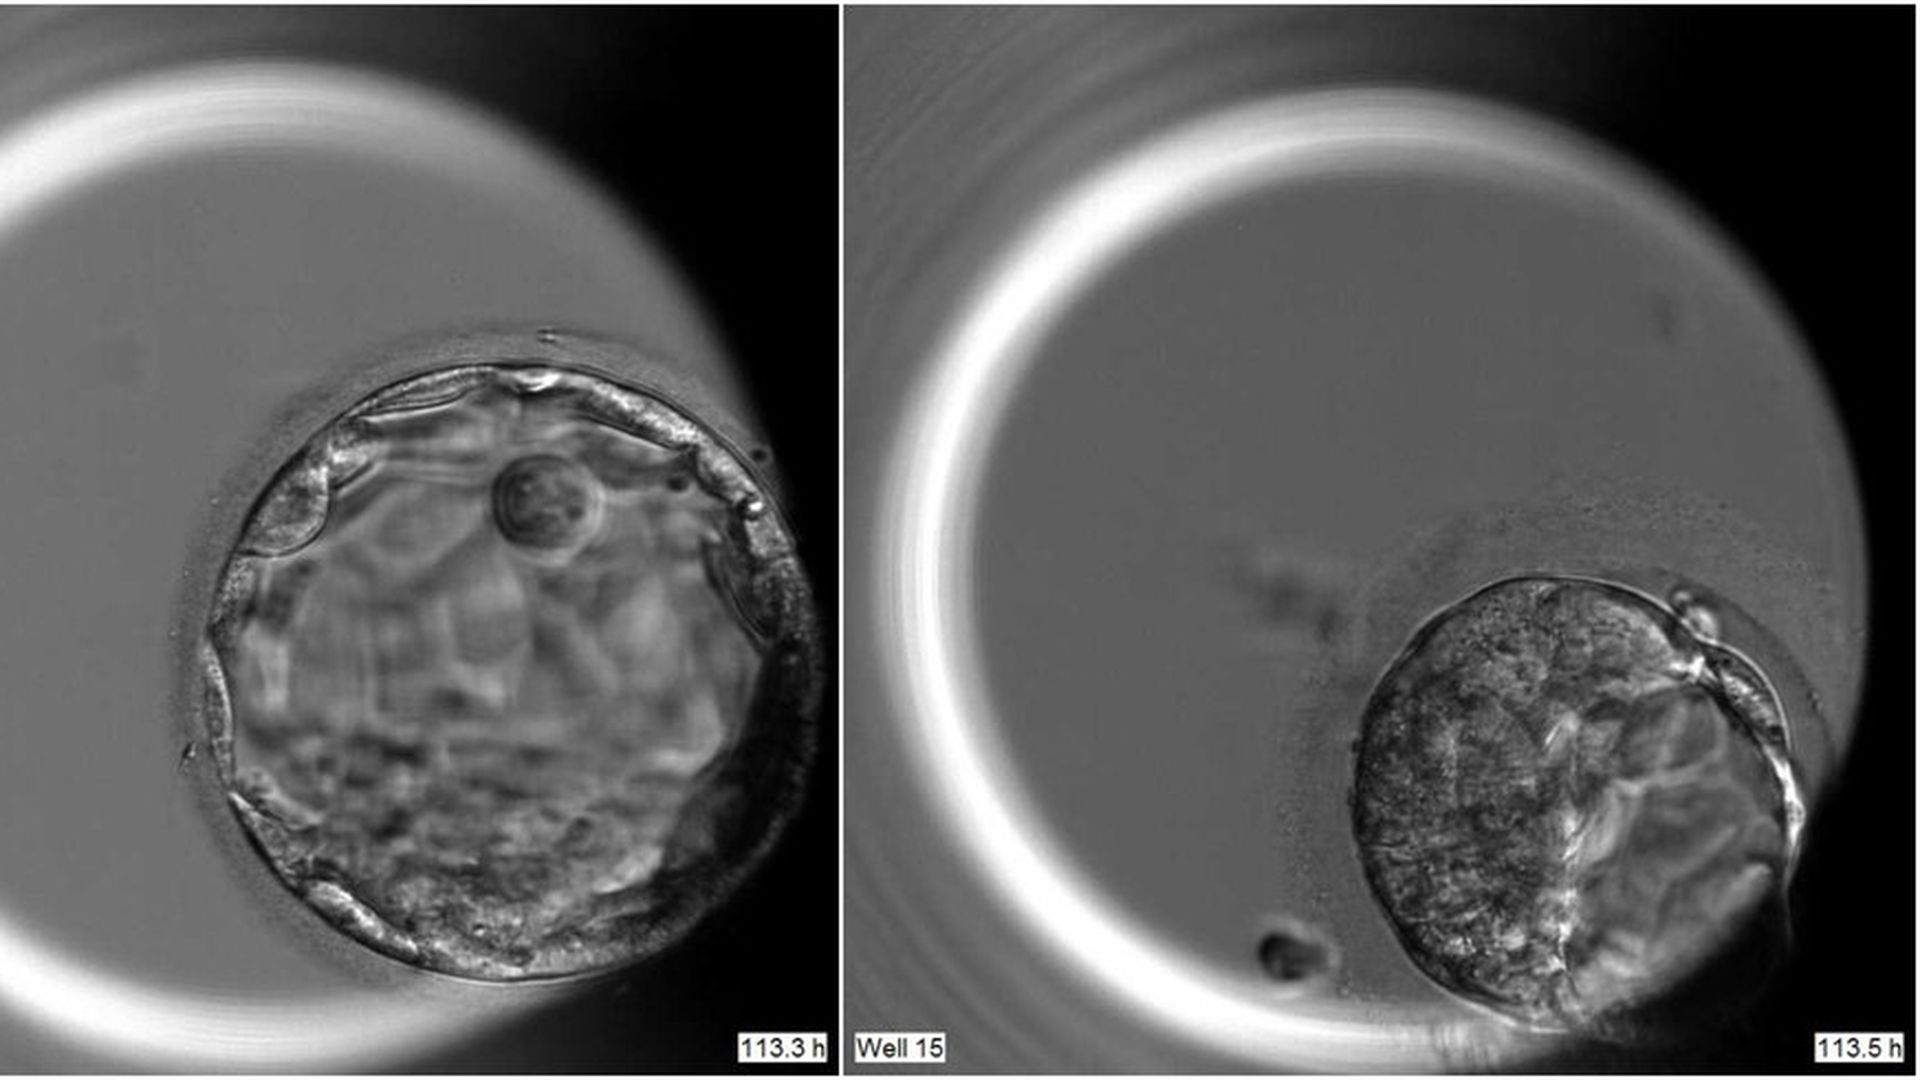

Human embryo on the 5th day of development with OCT4 function in tact (left) and without. Credit: Kathy Niakan / Nature.

What they did: Researchers knew that a protein called OCT4 was activated in the first few days of human development. They used CRISPR gene editing to knock out the gene encoding for OCT4 in 41 human embryos left over after IVF treatments and watched what happened over the next seven days (they stopped the experiments at that point). When the gene lost its function (the editing technique worked about 80% of the time), most of the embryos (about 80%) underwent early cell divisions but failed to form the ball of 200 cells. (The 20% that did reach that stage partially expressed the gene encoding for OCT4.)